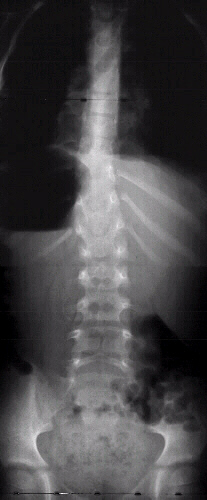

This 7 year old male presented to the cerebral palsy clinic with mild development delay, hyperactivity, and kyphosis. On physical examination he was slightly small for age (5th percentile weight for age, 10th percentile height for age) and had hyperactivity. He had no clonus or spasticity but a slightly clumsy gait. An MRI and plain x-rays were ordered (image 1, 2 & 3). After two years of brace wear the kyphosis increased to 78 degrees(image 4). The child is complaining of the brace and starting to refuse brace wear.